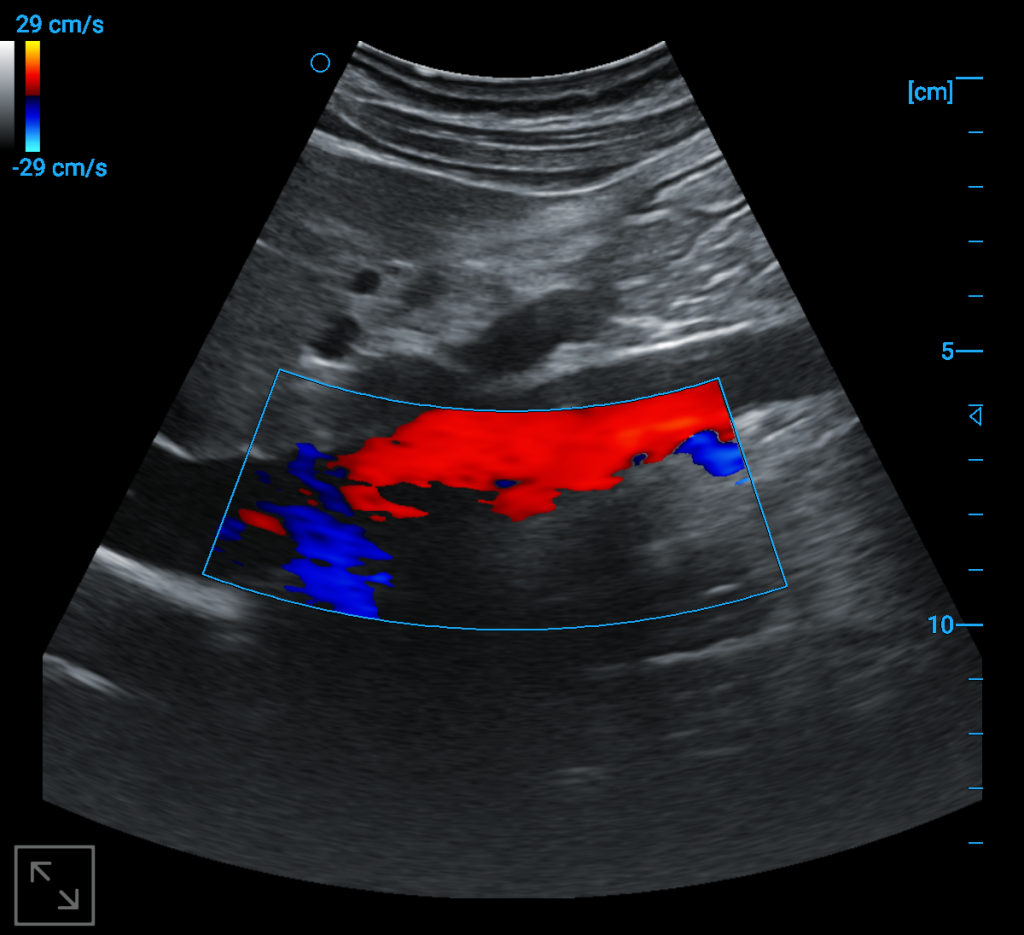

Abdominal aorta blood flow